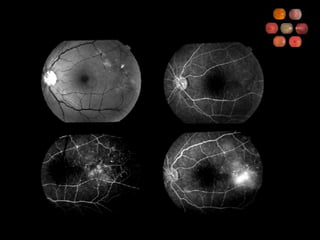

47 yo 20/20 referred by internist

47 yo 20/20referred by internist

Ocular Ischemic Syndrome What percent carotid obstruction is typically required to cause OIS? 90% Describe the symptoms Gradual visual loss Aching pain Prolonged recovery following bright light exposure What are anterior segment findings? Iris neovascularization (67%) AC cellular reaction (20%)

Ocular Ischemic Syndrome Describe the posterior segment findings Narrowed arteries Dilated, non-tortuous veins Mid-peripheral retinal hemorrhages, microaneurysms Neovascularization What are the fluorescein angiographic findings? Delayed choroidal filling (60%)  Delayed arteriovenous transit (95%) Vascular staining (85%) What is the 5-year mortality rate and what is the most common cause of death? 40% Cardiovascular disease

Ocular Ischemic SyndromeWhat percent carotid obstruction is typically required to cause OIS? 90% Describe the symptoms Gradual visual loss Aching pain Prolonged recovery following bright light exposure What are anterior segment findings? Iris neovascularization (67%) AC cellular reaction (20%)

Ocular Ischemic SyndromeDescribe the posterior segment findings Narrowed arteries Dilated, non-tortuous veins Mid-peripheral retinal hemorrhages, microaneurysms Neovascularization What are the fluorescein angiographic findings? Delayed choroidal filling (60%) Delayed arteriovenous transit (95%) Vascular staining (85%) What is the 5-year mortality rate and what is the most common cause of death? 40% Cardiovascular disease